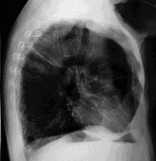

만성 폐쇄성 폐질환은 증상, 진찰, 방사선 사진, 폐 기능 검사 등을 종합하여 진단합니다. 진찰 소견상 특징은 술통형 흉곽입니다. 이는 흉곽이 과다 팽창하여 흉곽의 전후경이 늘어나면서 둥글게 되는 것입니다. 호흡수가 빠르고 얕으며 호기 시간이 길어지고 보조 호흡근을 사용한 호흡을 합니다.

방사선 사진은 아주 심한 만성 폐쇄성 폐질환을 제외하면 정상에 가깝습니다. 방사선 사진은 다른 병이 아닌지를 확인하기 위하여 촬영합니다.